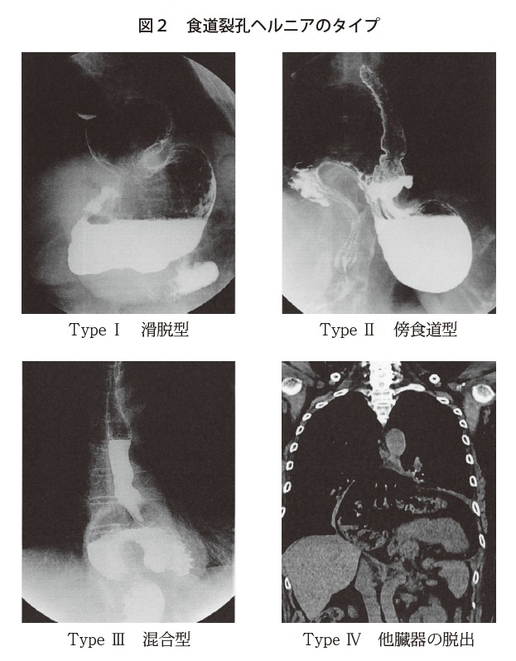

食道裂孔ヘルニアは大きく分けて4つのタイプがあります(図2)。TypeⅠは滑脱型といって、上にだけ出るタイプ。TypeⅡは傍食道型といって、食道胃接合部の位置は通常の位置にありますが、その横から出てしまうタイプ。TypeⅢは混合型で、上と横に出てしまうタイプ。TypeⅣは、胃以外の臓器、一番多いのは横行結腸ですが、横行結腸や大網、ひどくなると脾臓、すい臓が出てしまうものもあります。